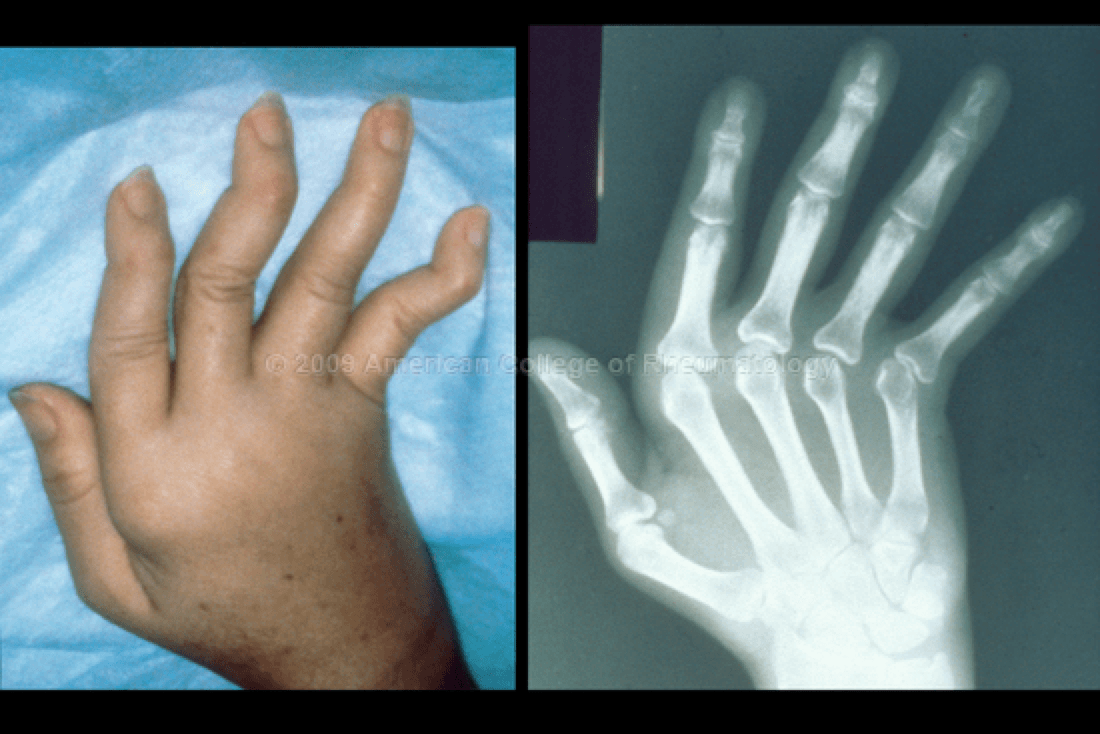

What is Jaccoud Arthropathy?